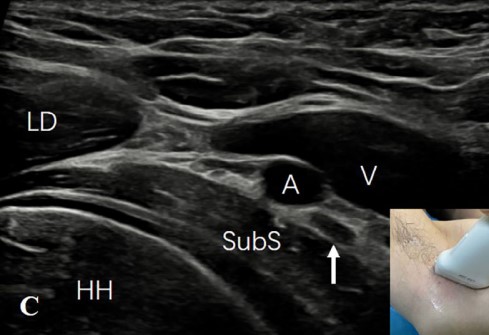

3) 腋动脉后方:探头沿腋神经向内侧移动至腋血管后方,有时可见腋神经由臂丛后束发出(图3C)。将探头与腋神经平行并轻调探头位置,可见旋肱后动脉位于腋神经旁,并可追溯至其起源于腋动脉(图3D)。

图3C:沿腋神经(AN)(白色向上箭)向内侧移动探头至腋动脉(A)和静脉(V)的后方。

图3D:轻调探头位置,可见后旋肱后动脉(PCA)位于腋神经(AN)(箭头)旁,可追溯至其起源于腋动脉。